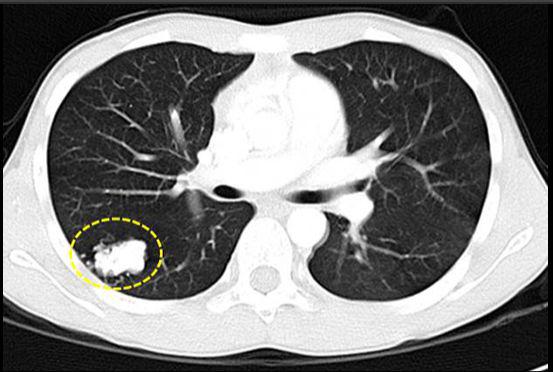

在生活中经常会有人查出肺部结节,这种是不是肺癌的预兆呢?肺癌帮APP里也经常有人留言,肺癌小结节会不会转成癌呢?这些疾病的信号引起了...【查看详情】